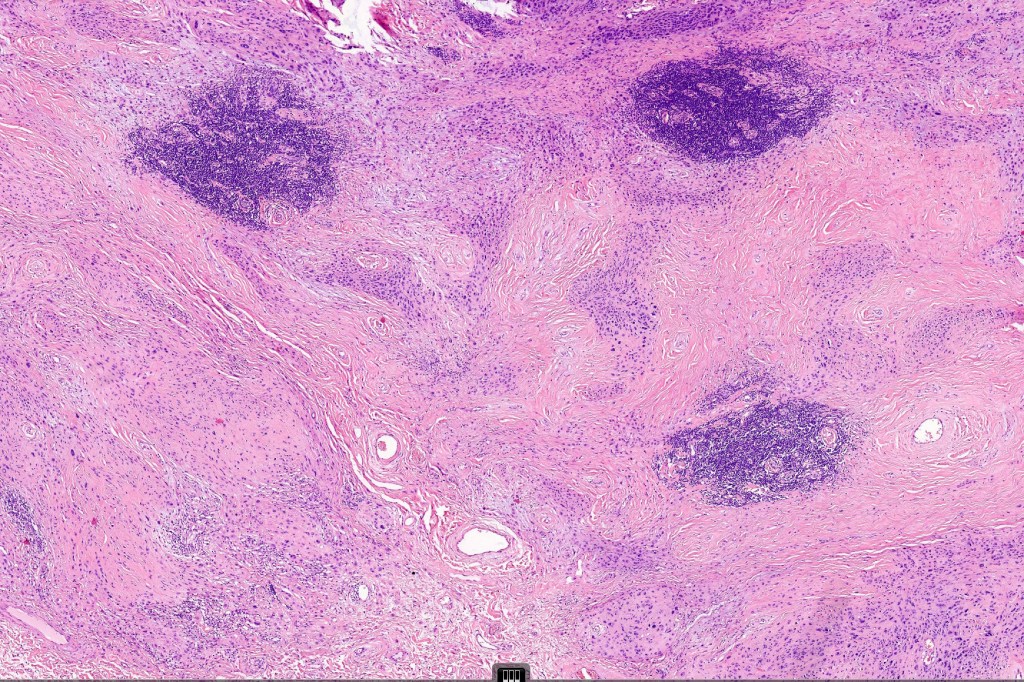

This is a rare variant of melanocytic nevus, so-named because it shares some of the features of ancient schwannoma and not because of its age! It most often arises on the face of older patients as a flesh colored or erthematous nodule. Its importance is that it may be mistaken as melanoma by the unwary.

Histological features

•Dome shaped silhouette

•Sclerosis with hyalinization

•Vascular ectasia sometimes with thrombosis & hemorrhage